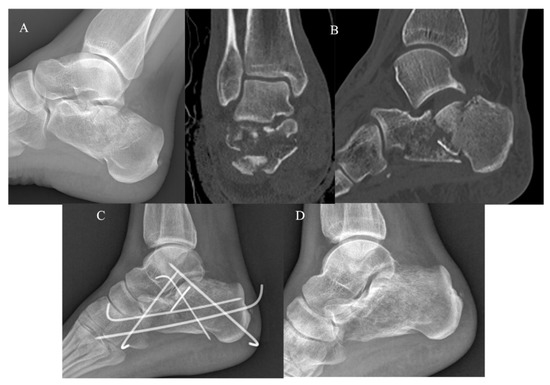

The KG (Figure 2) and PG (Figure 3) consisted of 20 and 22 CF, respectively. The group demographic characteristics and specific mean final follow-up are summarized in Table 1.

Figure 2.

Mini-open approach and K-wire fixation. (A) Pre-operative radiographs; (B) pre-operative CT scan in coronal and sagittal plane showing a Sanders III CF; (C) post-operative radiograph control; (D) post-operative radiographs at 4-year follow-up.

At the final follow-up of 54.6 ± 16.8 months, the KG group (50% of the total pool) presented a mean post-operative AOFAS score of 70.7 ± 11.9 (45–83), mean SF-12 PCS score of 45.7 ± 6.8 (28.4–55.4), and SF-12 MCS score of 54.7 ± 9.9 (31.9–63.5). No patients underwent subsequent re-interventions and two patients (10.5%) presented minor complications (one case of delayed wound healing and one post-traumatic subtalar osteoarthritis).